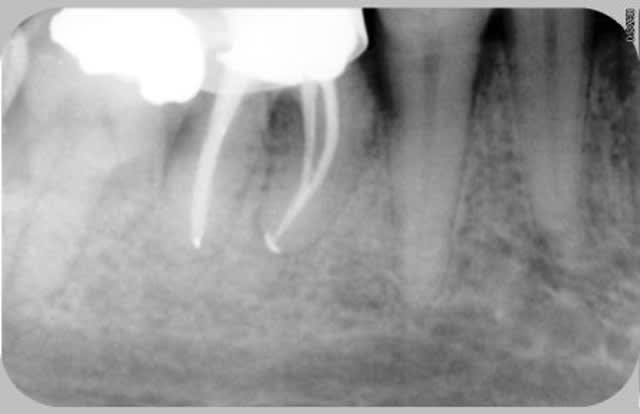

08/11/2008 à 14h14

Et celle là elle est pas belle???

Une heure, je trouve le 4ème canal,je le cathétérise jusqu'au bout, je me dis ça démarre bien, on y va tranquille, digue, edta hypo par litres etc etc.

ET?????

Le dernier instrument (heureusement le dernier!!), il pète dans le canal MV2.

AGGRRRRRRRRRRRRRRRRRRRRRRRRRRRRRRRRRR LES BOULES !!!!!!!!

J'en ai marre, je les vérifie à la loupe, je ne force pas, et de temps en temps j'en casse.

Et comme je ne dois pas être très doué j'arrive à passer à côté une fois sur mille.

J'ai envie d'essayer un autre système FKG, qui a l'air bien, je l'ai acheté il y a six mois, pas eu le temps de mettre en pratique.

Pour ce qui est du prix, quand je dévitalise, c'est que la dent a une énorme carie et donc, sauf exception, c'est couronne, donc le prix de l'endo je m'en fous, c'est pour moi un acte global, je fais l'empreinte dans la même séance de 2 heures.

Mais bon quand tu sens que tu vas te faire une belle endo et que ça se finit comme ça , ça te fout un peu ta journée en l'air.

Ce qui me gonfle aussi c'est que je n'arrive pas à joindre ma radio, il y a un post là dessus, j'y vais voir et je reviens.

Dsc 0022 zyz4bz - Eugenol

Fred

08/11/2008 à 15h45

Ca marche!!!